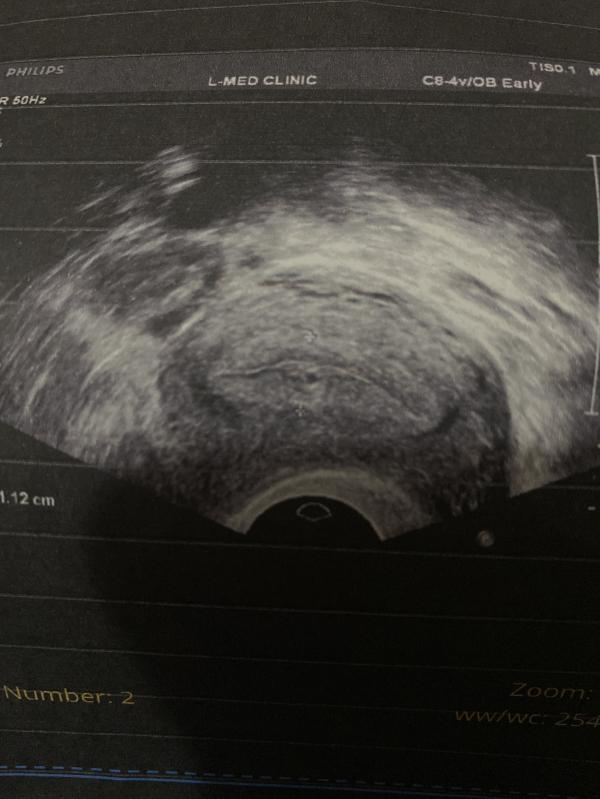

Спасибо большое 🥰 ну напугали ж внематочной, так понеслась душа в рай😂

Терпеть долго не могла😂ну когда сказали что есть вероятность внематочной, конечно будет паника , в тот же день приходила девочка в клинику, та самая проблема, и в итоге оказалась внематочная, уже прооперировали, поэтому ясное дело что предупрежён значит вооружён 😄спасибо вам большое ❤️